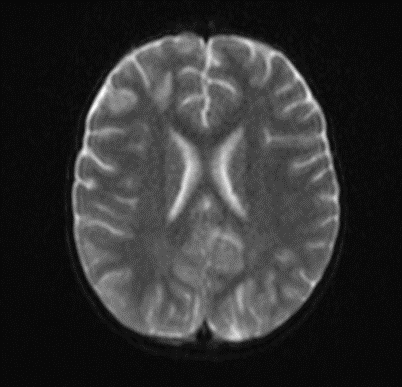

The MRI of the brain revealed the following findings:

- Bilateral subcortical zones, predominantly in the occipital region, exhibiting confluent hyperintense signals on T2 and FLAIR sequences, accompanied by edema.

- A suspected area of cytotoxic edema in the superior parietal lobe.

- High signal intensities on T2 and FLAIR sequences observed in the centrum semiovale, right of the corpus callosum body, and bilaterally in the frontal gyrus, without diffusion restriction.

- In the supraventricular region, extending inferiorly from the projection of the postcentral gyrus into the subcortical white matter to the posterior part of the corpus callosum body (excluding it), and in the left superior temporal lobe, there was a cortico-subcortical lesion characterized by cytotoxic edema and restricted diffusion.

Picture 3.